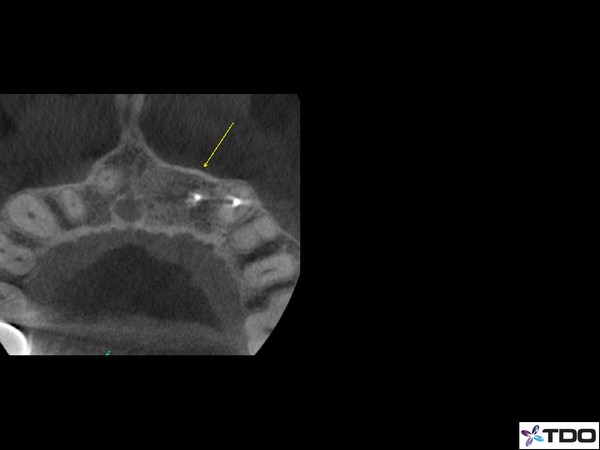

Blog Image